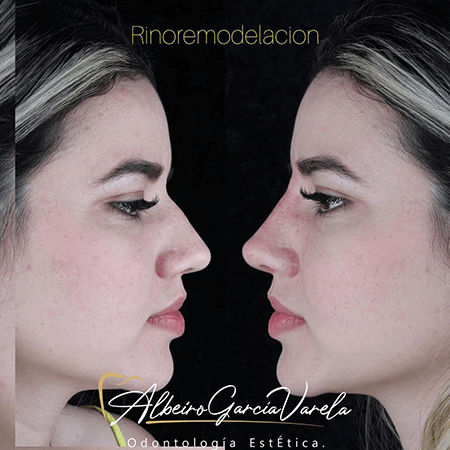

Cuento con más de 15 años de experiencia ofreciendo tratamientos odontológicos integrales en Santa Marta, enfocados en elevar la estética, la salud oral y la confianza de mis pacientes. Mis servicios incluyen diseño de sonrisa, ortodoncia, implantes dentales, odontología estética, lentes cerámicos, coronas libres de metal, tratamientos para bruxismo,…

Galería de antes y después

- Armonización orofacial Instituto Ziroldo Curitiba , Brasil 2021